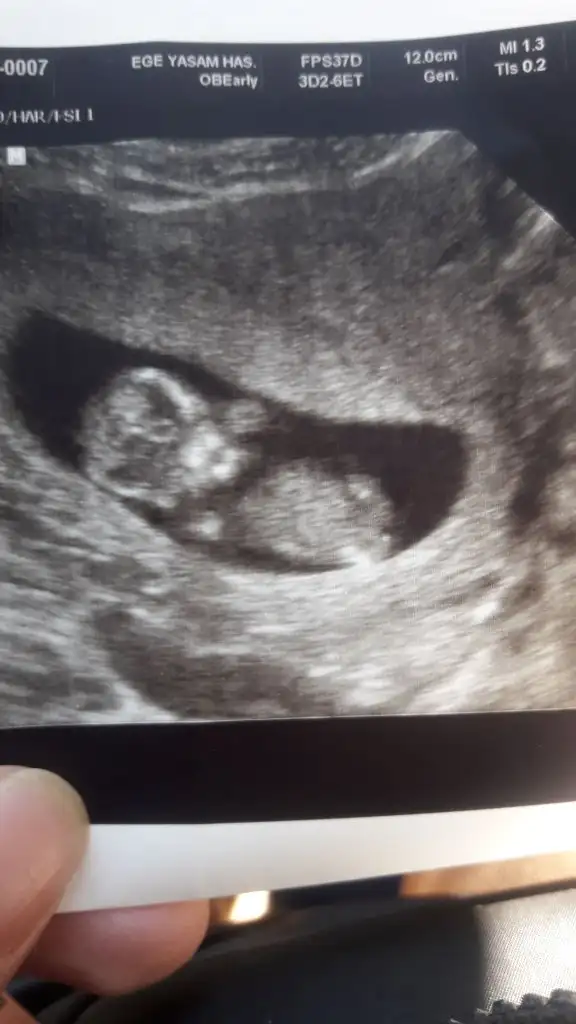

Kız sanki ama nubu ne dik nede paralel poposu yukarı olduğu için etkilemiyorsa kız gibi gibi baska USG de paylaşınCnm arkadaşımın bebeğini yorumlarmısınIkra meyra

Net değil USG 11-12-13. Hafta olmalıEki Görüntüle 2668963 Merhaba, ben kız diye düşündüm ama sizce nedir?

Nubu kız gibi görüntüsü erkek gibi

Kız gibi emin olamadım